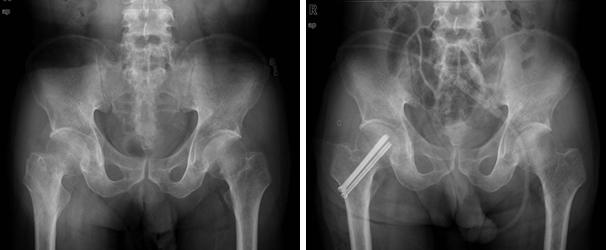

다발성 핀 고정술 다발성 핀 고정술 이미지

인공 관절 반치환술 인공 관절 반치환술 이미지